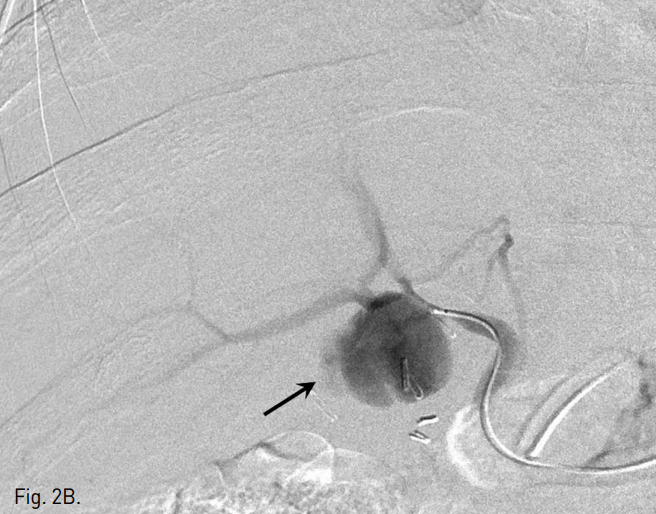

복강동맥조영술에서 우간동맥의 분지부에 인접한 위치에 가성동맥류를 확인하였다(Fig. 2A, B). 6F Shuttle guiding catheter(Cook, Bloomington, IN, USA)로 교체 후에 Stent-graft(4×26mm, JoStent GraftMaster®, JoMed, Germany)를 가성동맥류가 있는 우간동맥에 위치시키고, 풍선카테터(Ultra-thin Diamond,Boston Scientific, Galway, Ireland)를 사용하여 확장시켰다. 시술 직후 시행한 복강동맥조영술에서 동맥류는 관찰되지 않았다(Fig. 2C).

Fig. 2

Celiac (A) and hepatic angiogram (B) show the pseudoaneurysm (arrows in A and B) at distal part of the right hepatic artery near the origin of the right posterior hepatic artery. (C) On hepatic angiogram after stent-graft placement (arrow), the pseudoaneurysm is completely excluded.